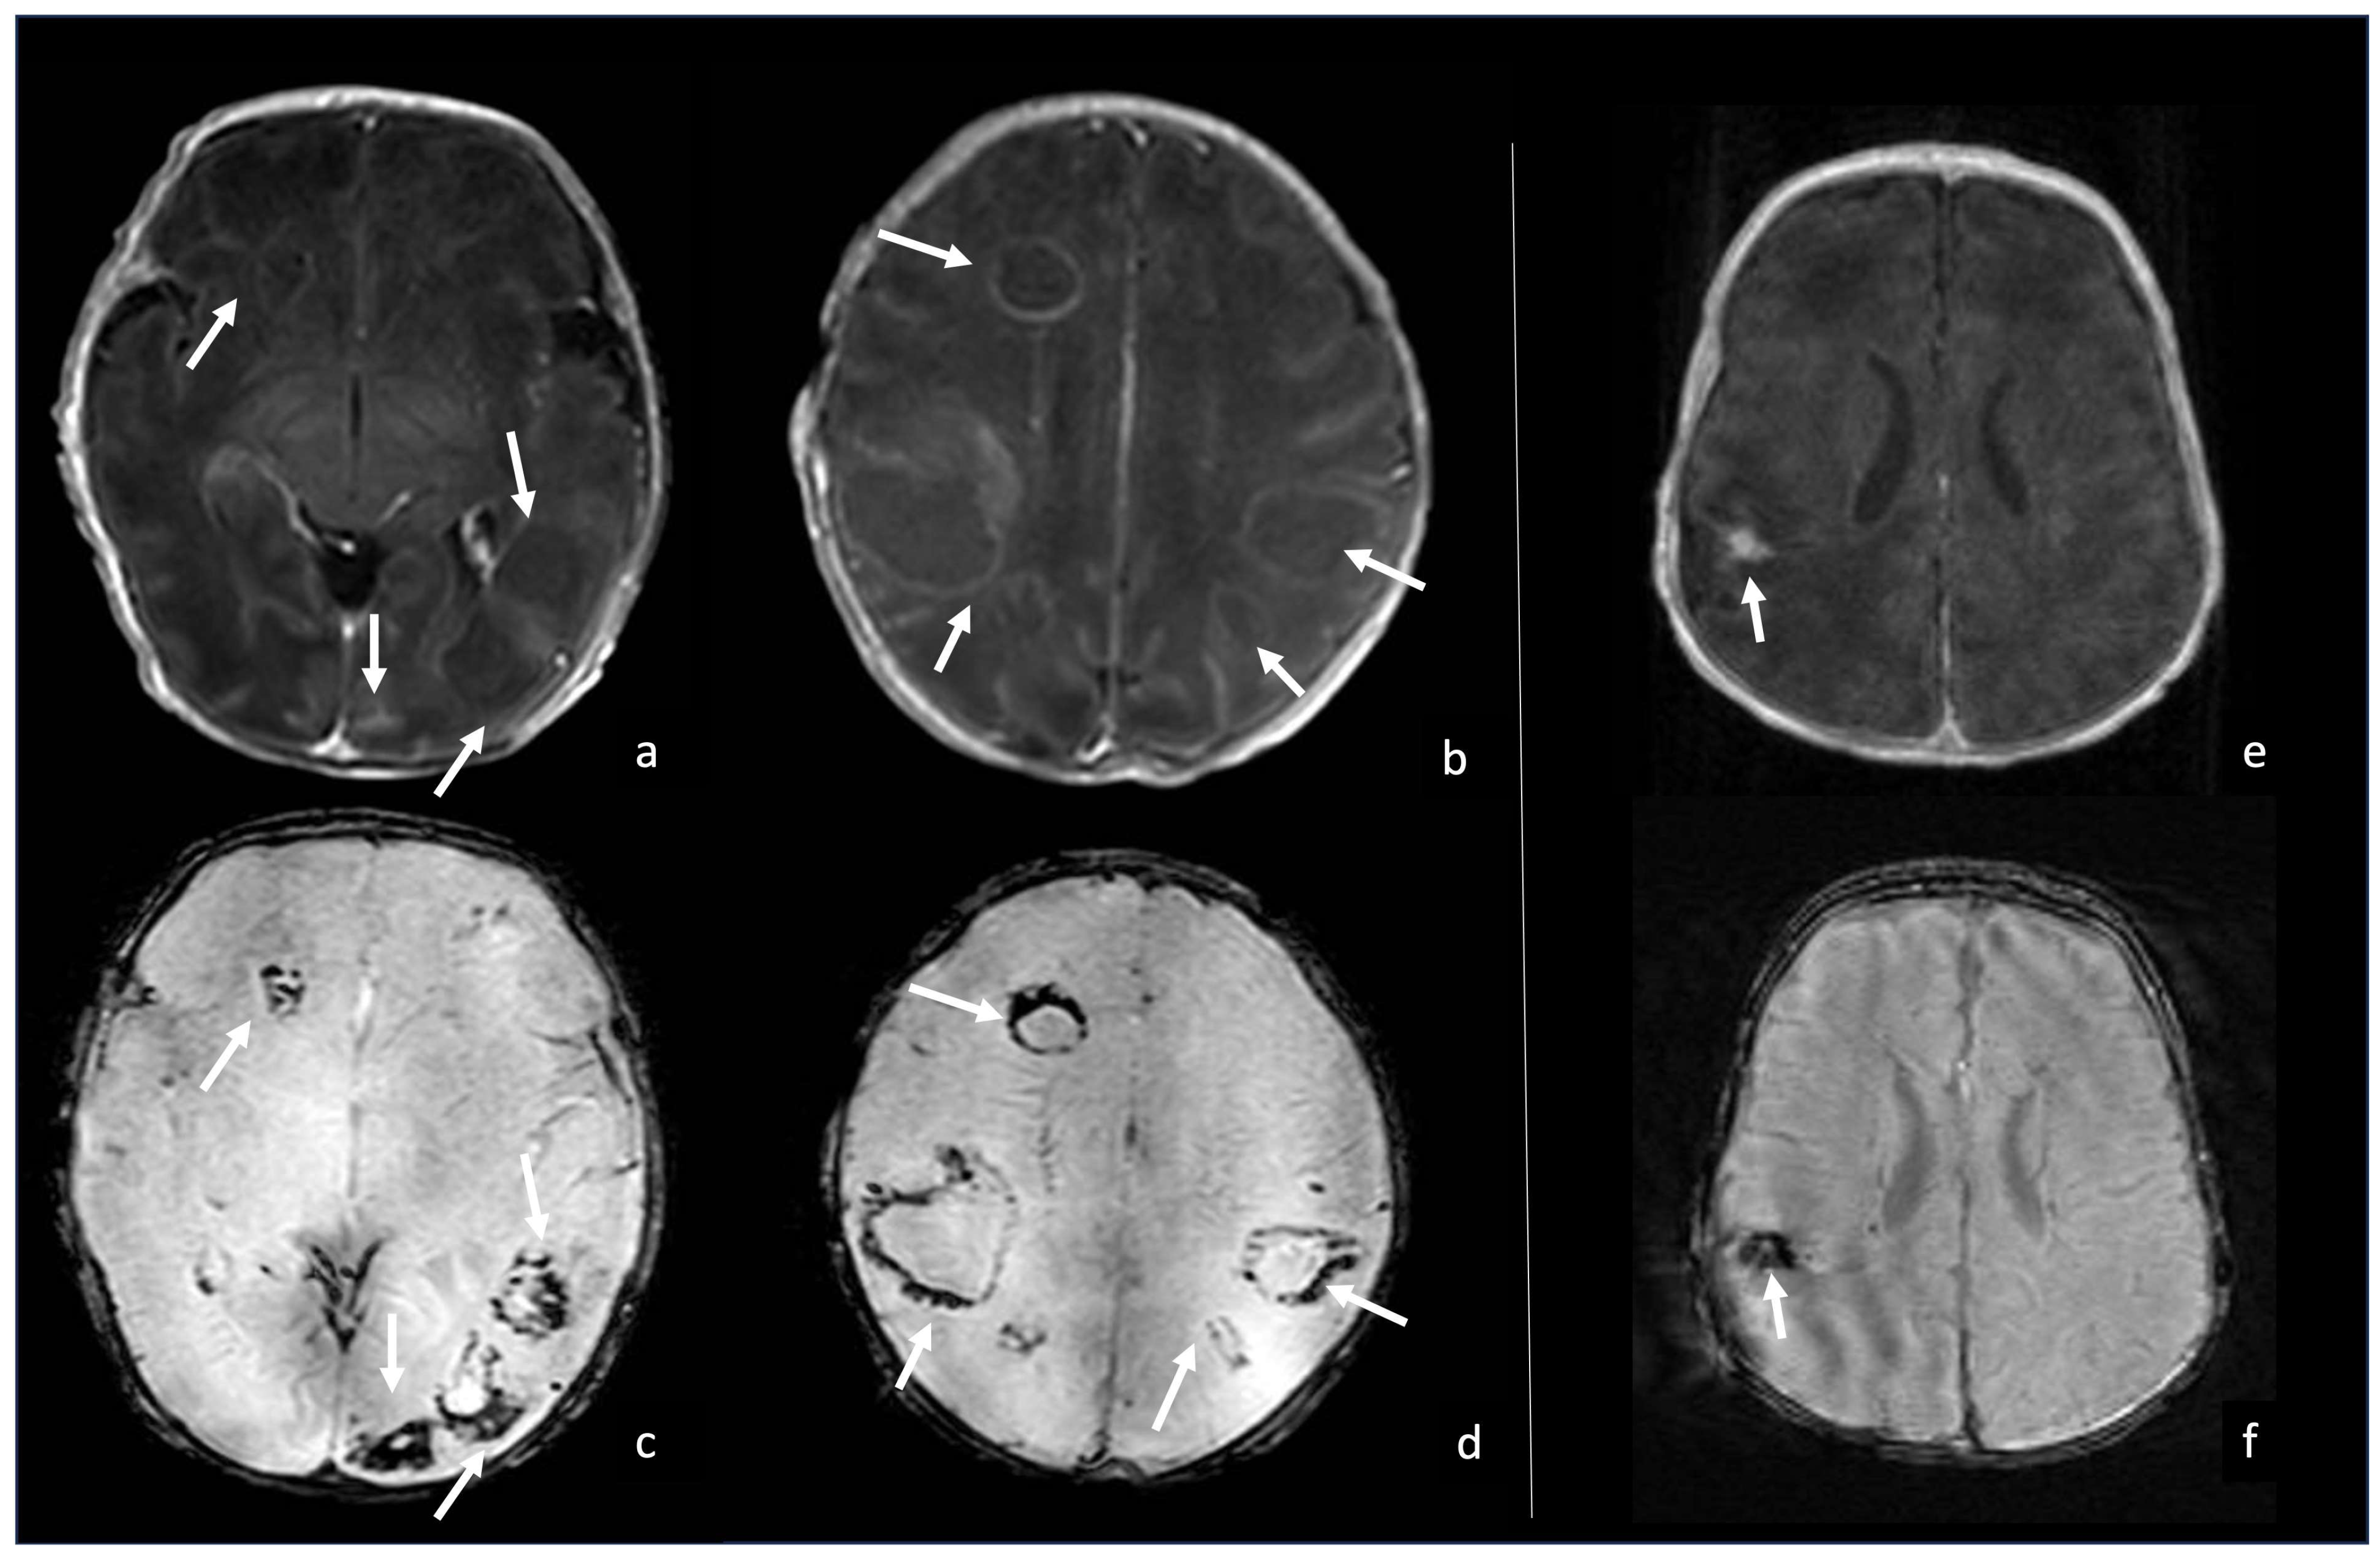

7.3. Gram-Negative Bacteria and Abscesses

7.4. Gas-Producing Bacteria and Pneumocephalus